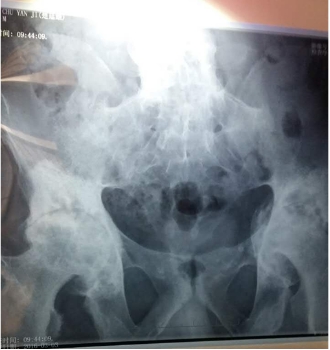

(图:患者提供的3月3日检查的片子)

[由片子可见,楚先生已经出现强直性脊柱炎合并股骨头坏死,股骨头表面粗糙、骶髂关节已经炎性融合,左侧关节间隙变窄、右侧关节间隙消失,活动受限严重。这也是患者无法弯腰、不能活动的主因。]

(图:患者提供的骶髂关节、股骨头部位片子)医学解读:患者强直导致周边骨质纤维化,股骨头出现局部塌陷,左侧塌陷严重,所以医生建议行关节置换手术,改善患者的活动功能。

[强直性脊柱炎合并股骨头坏死几率约为:15%左右,特别是发展到晚期。所以也建议强直患者,一定要早治疗,特别是患病前5年,是治疗最佳时机,不应等到疾病恶化后再寻求治疗,不仅费用高、治疗难度大,还会引发多种并发症。]